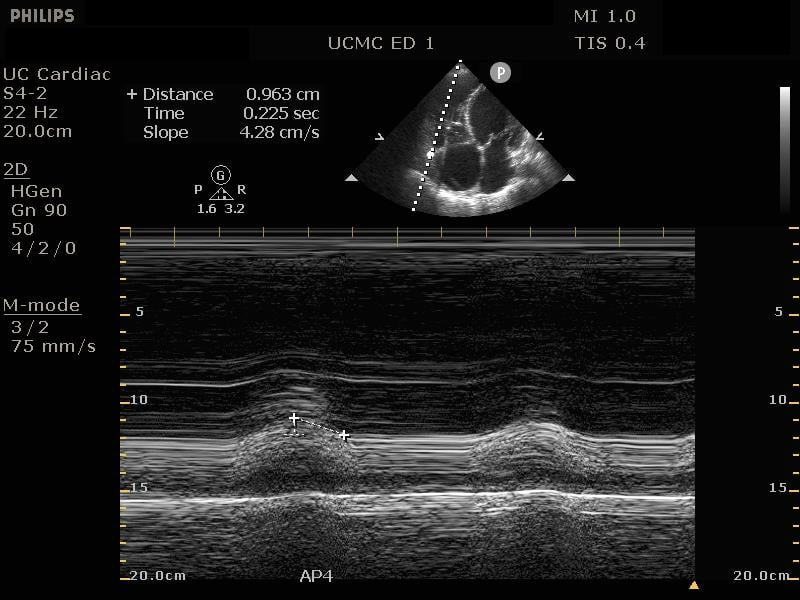

From jetem.org

TAPSE, Ultrasound 2. JETem 2018 JETem Tapse Ultrasound tapse measures the longitudinal movement of the lateral tricuspid annular plane during systole. tricuspid annular plane systolic excursion (tapse) can provide a point of care ultrasound assessment of right ventricular function. tricuspid annular plane systolic excursion (tapse) measures the longitudinal right ventricular function. in previous discussions we introduced how using the tricuspid annular plane systolic excursion. Tapse Ultrasound.